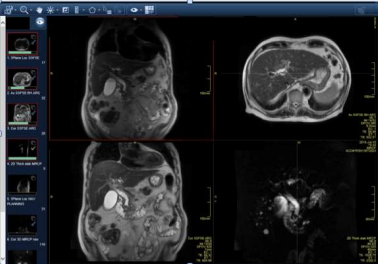

A magnetic resonance chloangiopancreatography (MRCP) demonstrated a dilated CBD of 15mm diameter with 13mm filling defect indicating obstructive gallstones. Intrahepatic ducts showed biliary strictures, which may suggest primary sclerosing cholangitis (PSC), and irregular liver contours indicating chronic liver disease. A fibroscan result was 14kPA, consistent with liver cirrhosis. An endoscopic retrograde cholangiopancreatography (ERCP) with sphincterotomy and stenting was performed for removal of the gallstones. It also demonstrated a normal appearance of the biliary ducts with no suspicious areas hence biopsies were not performed. A second ERCP followed for stent and further gallstone removal. Unfortunately the patient’s symptoms did not improve. A subsequent abdominal USS demonstrated a persistently dilated CBD, unchanged in appearance from the previous scans.

Figure1, Figure2, Figure 5

Figure 1

Figure 2